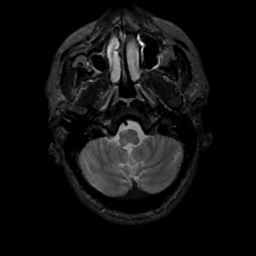

MR Study #3, February 24, 1991 -- Slice #7

[Home][Help][Clinical][Tour 1][Tour 2] Slice 7